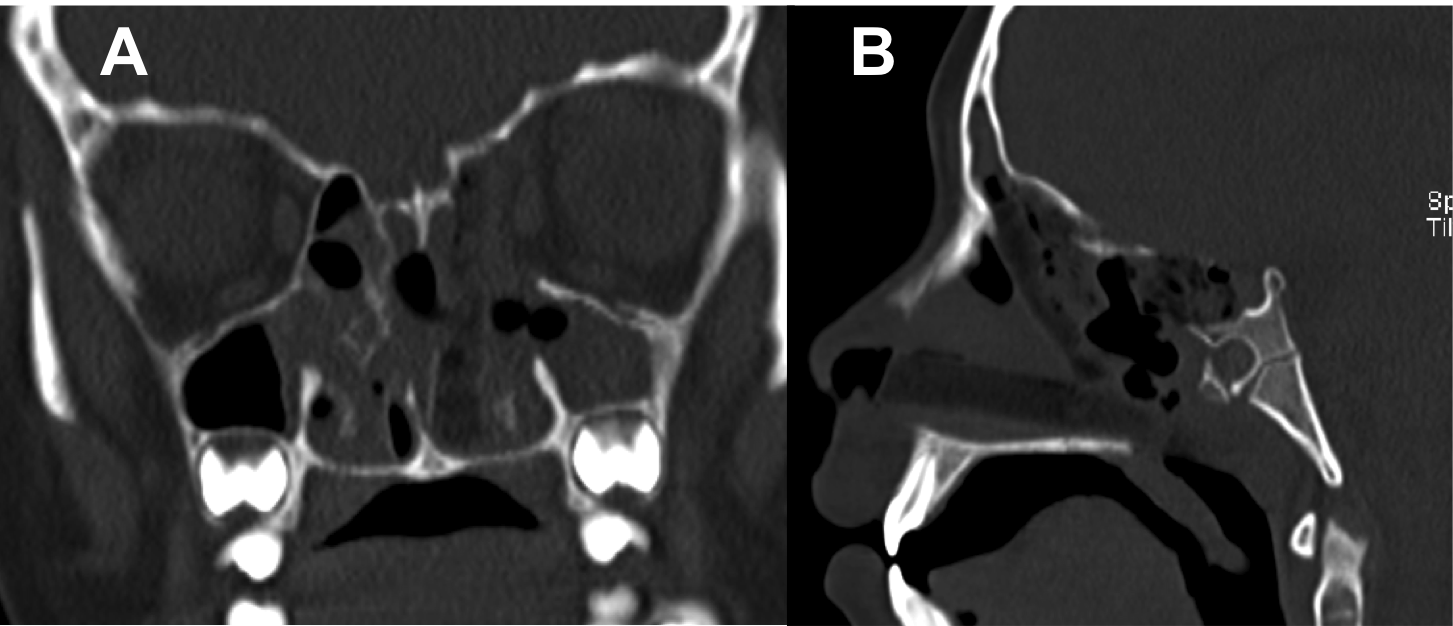

Introducción: La cirugía endoscópica endonasal se ha convertido en una herramienta fundamental para el manejo de patologías que comprometen la base de cráneo. En casos bien seleccionados, estas técnicas permiten resecciones quirúrgicas con una menor morbilidad sin comprometer los principios oncológicos de resección. Con el desarrollo de instrumental especializado, nuevas tecnologías y la experiencia de los cirujanos, la cirugía endoscópica endonasal se usa cada vez más en cirugía de base de cráneo en niños.

Resultados: Fueron intervenidos 8 pacientes entre los 2 y 14 años, con una edad promedio de nueve años y un seguimiento promedio de 16 meses. En el 75% se hizo una resección total del tumor. Un paciente requirió una reintervención y un paciente fue sometido a radiocirugía post-operatoria. 1 paciente falleció a pesar de múltiples intervenciones, quimioterapia y radioterapia.

Conclusión: La cirugía endoscópica endonasal para tumores de base de cráneo puede ser utilizada de forma segura en los pacientes pediátricos, es una técnica que en casos bien seleccionados pueden ofrecer excelentes resultados disminuyendo la morbilidad y complicaciones de las técnicas abiertas.